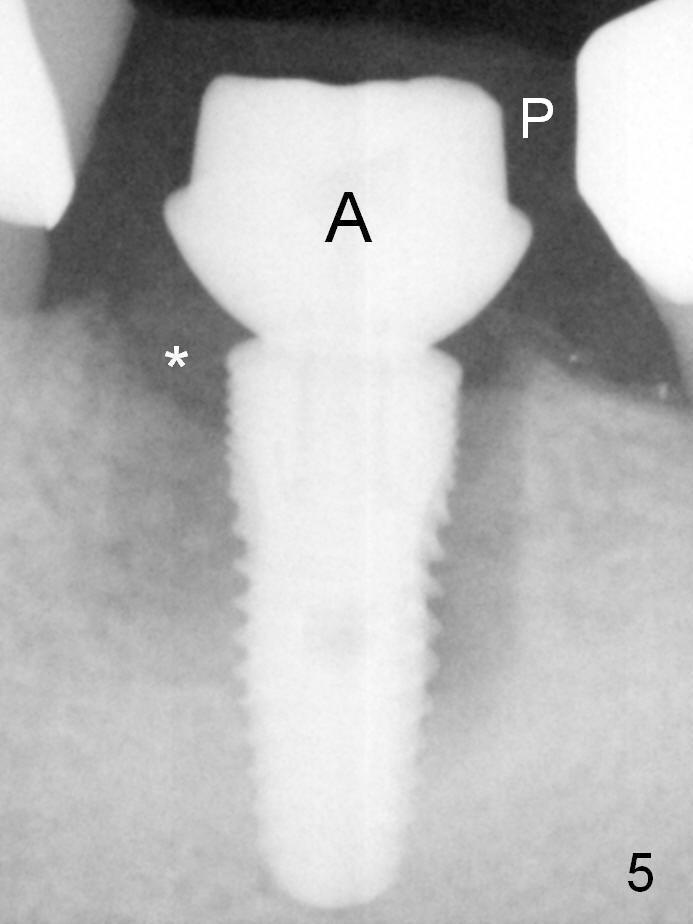

When a 5x12 mm bone-level implant is placed (Fig.4), there is a gap mesiobuccally, which is later filled with bone graft (Fig.5 *). A large abutment (7.8x4(3) mm) is placed immediately (Fig.5 A) for an immediate provisional (P) to close the sockets.